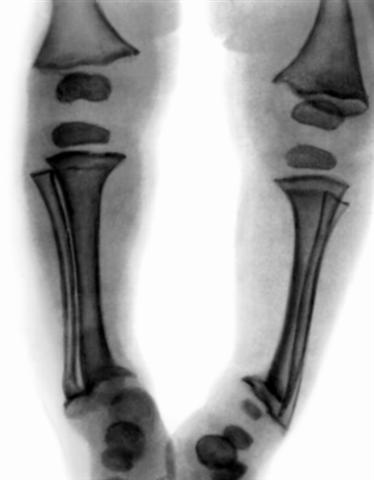

Рис. 5. Рентгенограмма нижних конечностей ребенка 1 года 5 месяцев: нечеткость костной структуры, расширены зоны предварительного обызвествления, неровный, бахромчатый субхондральный контур метафизов.